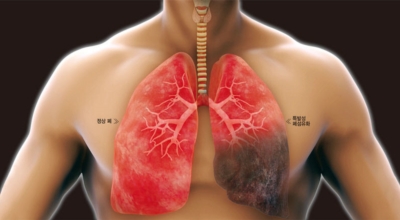

초기에 가벼운 기침으로 시작해 호흡하는 것조차 힘들어지게 되는데요 폐에 발생한 염증으로 인해서 폐의 신전성이 감소하고, 폐를 구성하는 폐포 세포가 망가져 적정 수준의 산소를 보관하지 못하기 때문에 호흡곤란이 유발될 수 있어요.

폐렴 : 누런 가래, 호흡곤란, 흉통 독감보다 증상이 오래 발생